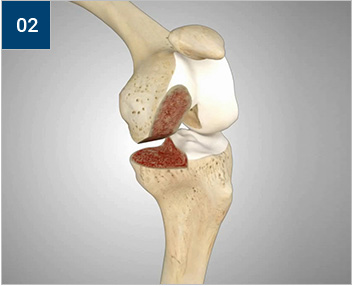

손상된 경골과 대퇴골 관절면

슬관절 앞부분을 절개한 후 손상된 경골과

대퇴골 관절면 부위를 정교하게 다듬어줍니다.

경골과 대퇴골의 밑단부에 특수 금속을 씌웁니다.

금속 사이에 연골 역할을 해줄 특수플라스틱을

삽입합니다.